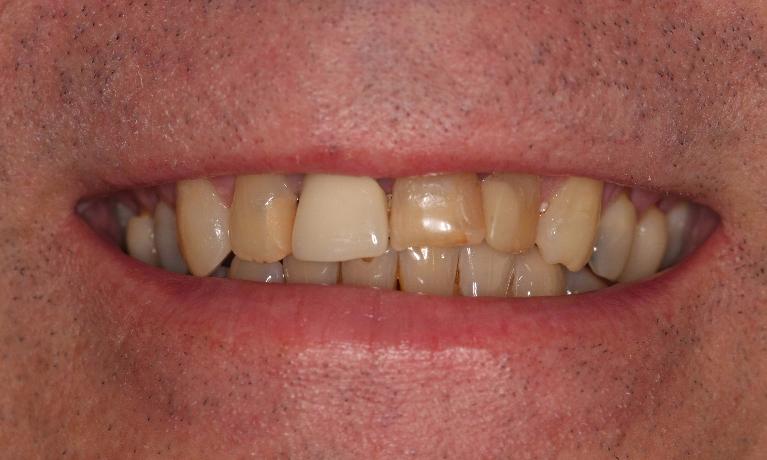

This young dad had four congenitally missing upper teeth. He had a quick orthodontic treatment and a large span bridge placed in as a teenager. He never smiles with teeth showing.

After many years of wear and tear, some of the work started to break and fail. We removed the defective bridges, managed to save all the existing teeth and placed four implant supported crowns in. The patient is very happy to be able to smile confidently now.